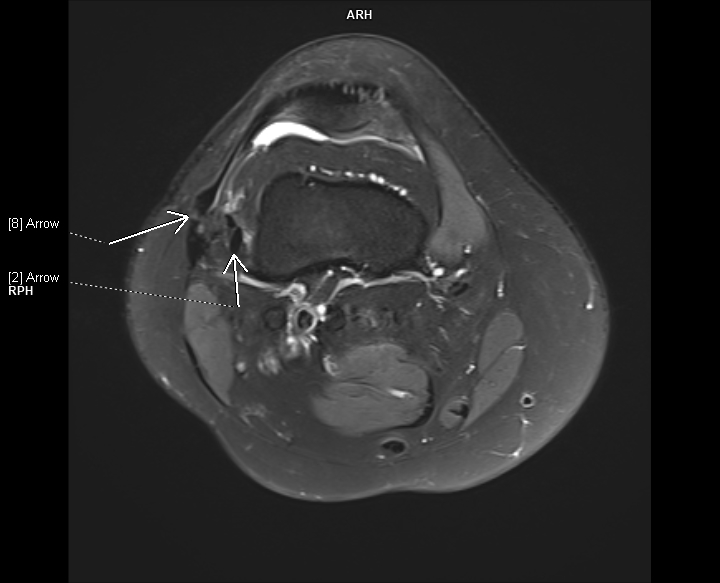

Figurile 1-3:  axial PD cu cu saturaţia grăsimii

Discuţie caz nr 107: la nivelul platoului tibial și posterior la nivelul condilului femural extern se evidențiază modificări de tip chistic în osul subcondral. În plus, a nivelul ligamentului colateral lateral se evidențiază o plajă limitată de lipsă de substanță în dreptul unei plaje de lipsă de substanță osoasă din condilul femural extern care este plombată postoperator.